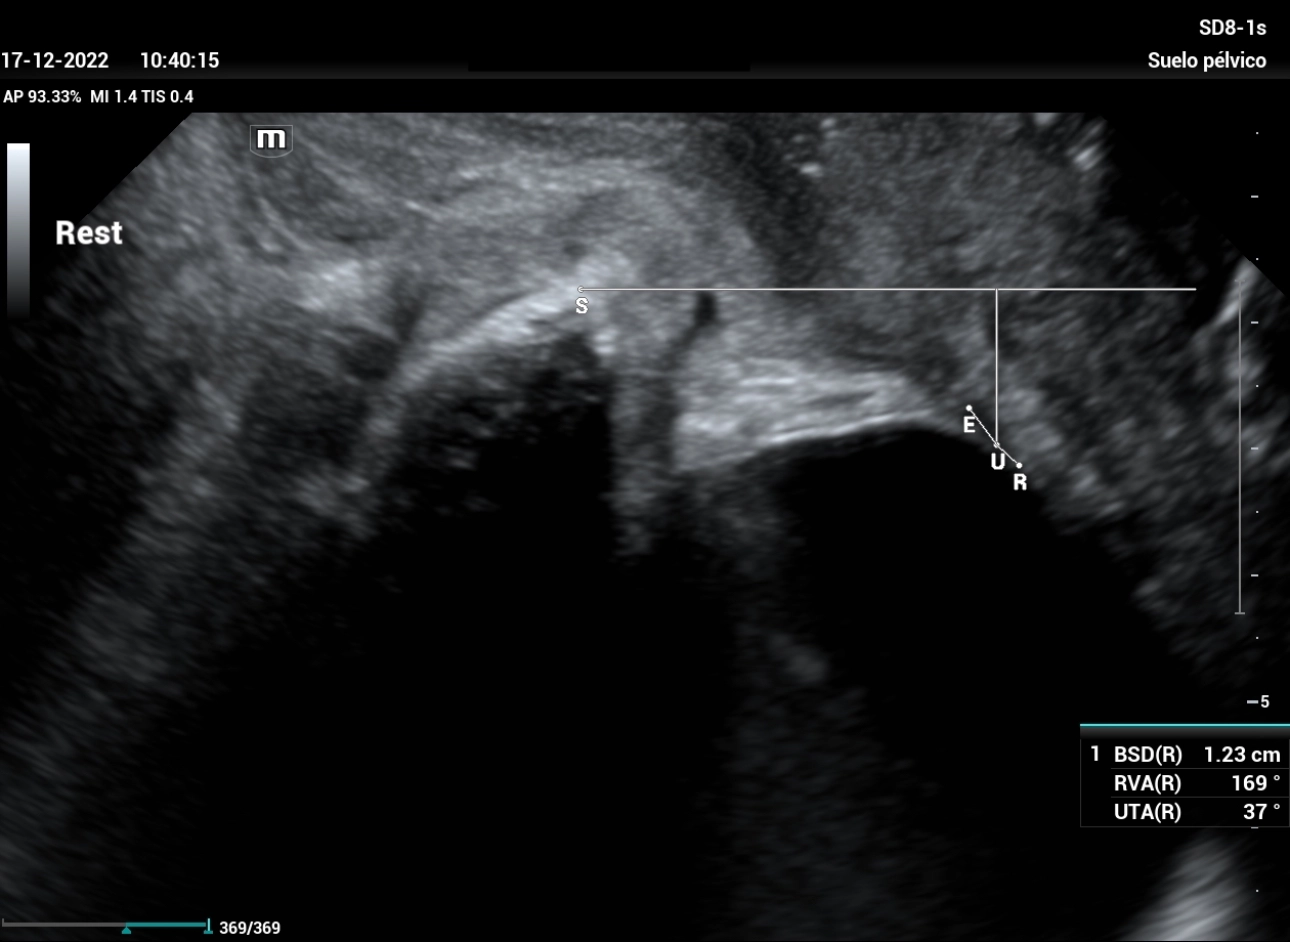

stress-urine-fig6

Figure 6: the image corresponds to the median sagittal section of the pelvic floor at rest, with magnification that allows the different structures to be studied to be correctly identified (symphysis pubis, bladder floor and urethra), with the measurement of the UTA and RVA angles.